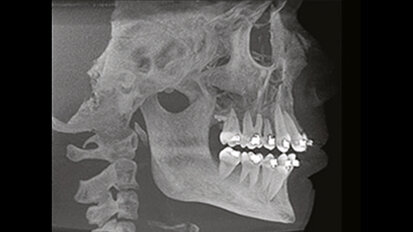

Použití technologie Cone Beam v ortodoncii

V době, kdy byla zubním lékařům představena výpočetní tomografie využívající kuželovitý paprsek záření (Cone Beam CT, CBCT), vstoupila v ...